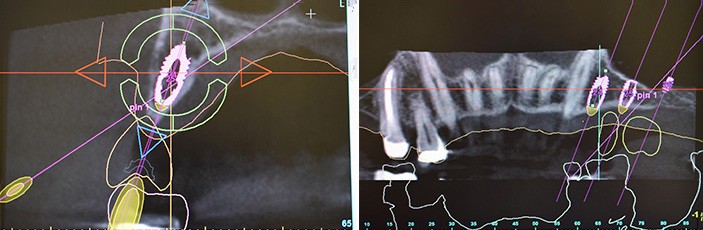

Dzięki cyfrowej implantologii możliwe jest wykonanie precyzyjnego skanu jamy ustnej oraz dokładne zaplanowanie położenia implantów dentystycznych, także względem siebie nawzajem. Pozwala to na przygotowanie indywidualnych szablonów chirurgicznych gwarantujących prawidłowe i bezpieczne umieszczenie implantów w kości, a także zaprojektowanie prac protetycznych. Jeszcze przed rozpoczęciem leczenia pacjent otrzymuje wizualizację planowanego efektu końcowego.